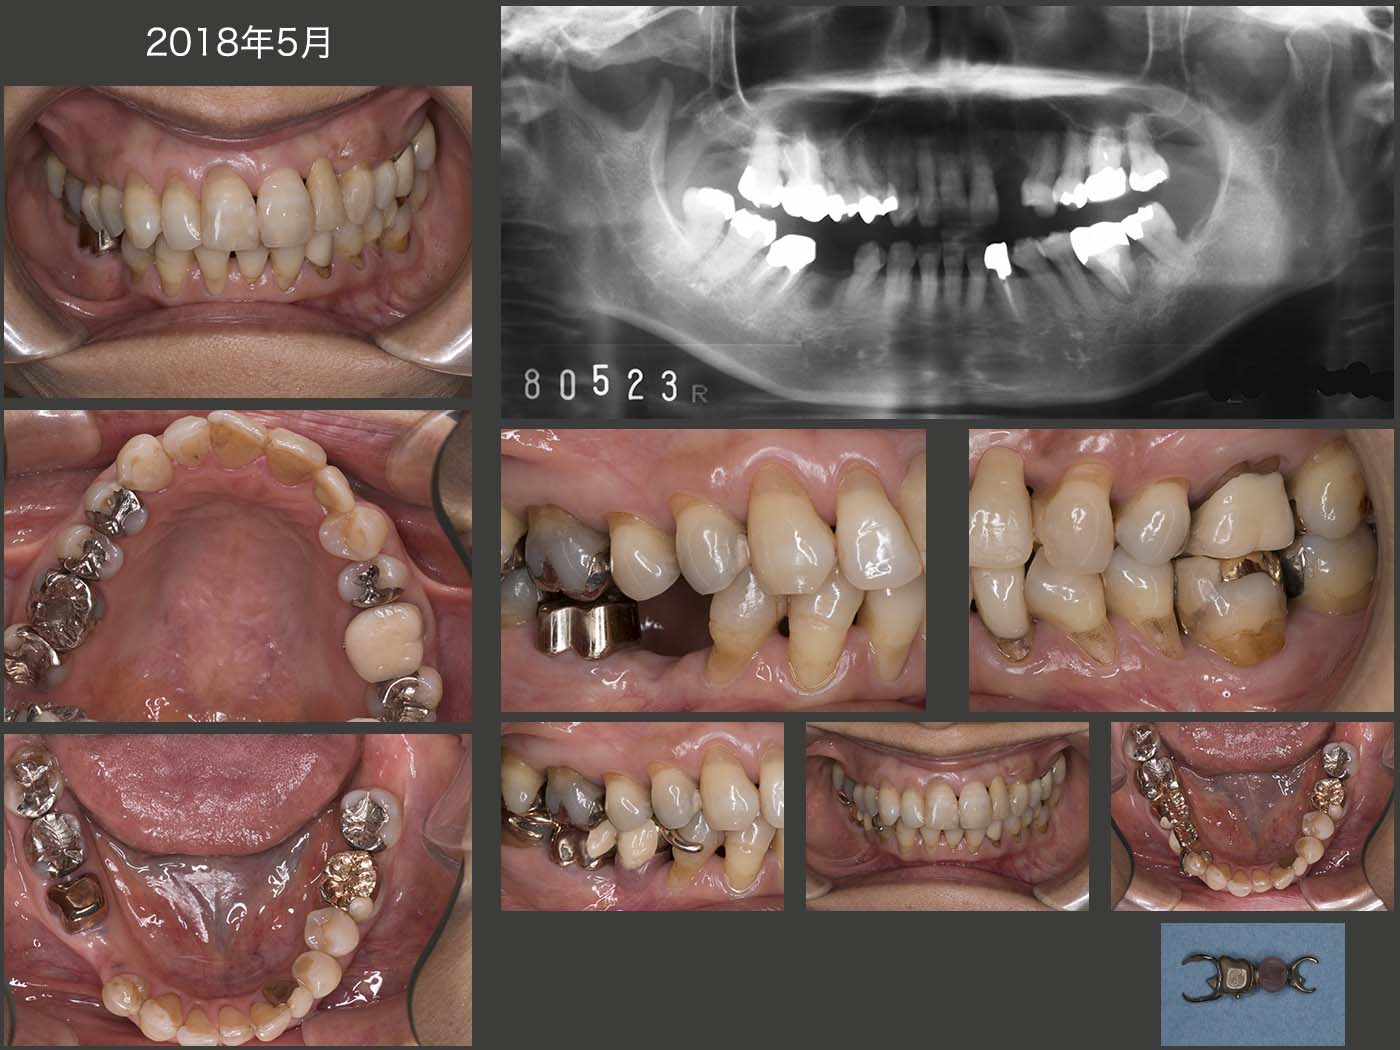

2018年5月の状態.右下にはコーヌス義歯を装着した.右下7のクラスプは,無髄歯である右下6に加わる水平力を少しでも担うことと,将来右下6が歯根破折等で失った場合,この部分に義歯床を足すのみで,そのまま使用できることを考えて付与した.

移植された左下6の経過であるが,2005年7月から19年12月までは,良好に経過した.(中段のデンタルX線写真は16年11月時).しかし,右下5を失い,左側で咀嚼する頻度が高くなったことが原因と思われるが,20年7月,頰側の歯周ポケットが10mmの値を示すようになってしまった.クラウンを外し,3ヵ月間自然挻出を期待したが,あまり変化がみられなかった.10月に歯周外科を施したが,頰側の骨が全く存在しなかった.12月現在,経過観察中であるが,歯周ポケットの改善(上皮性付着の獲得)がみられれば,左下7と連結固定(2次固定が望ましい)するつもりである.21年3月,左下5にクラスプ,左下6,7にコーヌス冠を用いた可撤式補綴装置の印象を採得した.